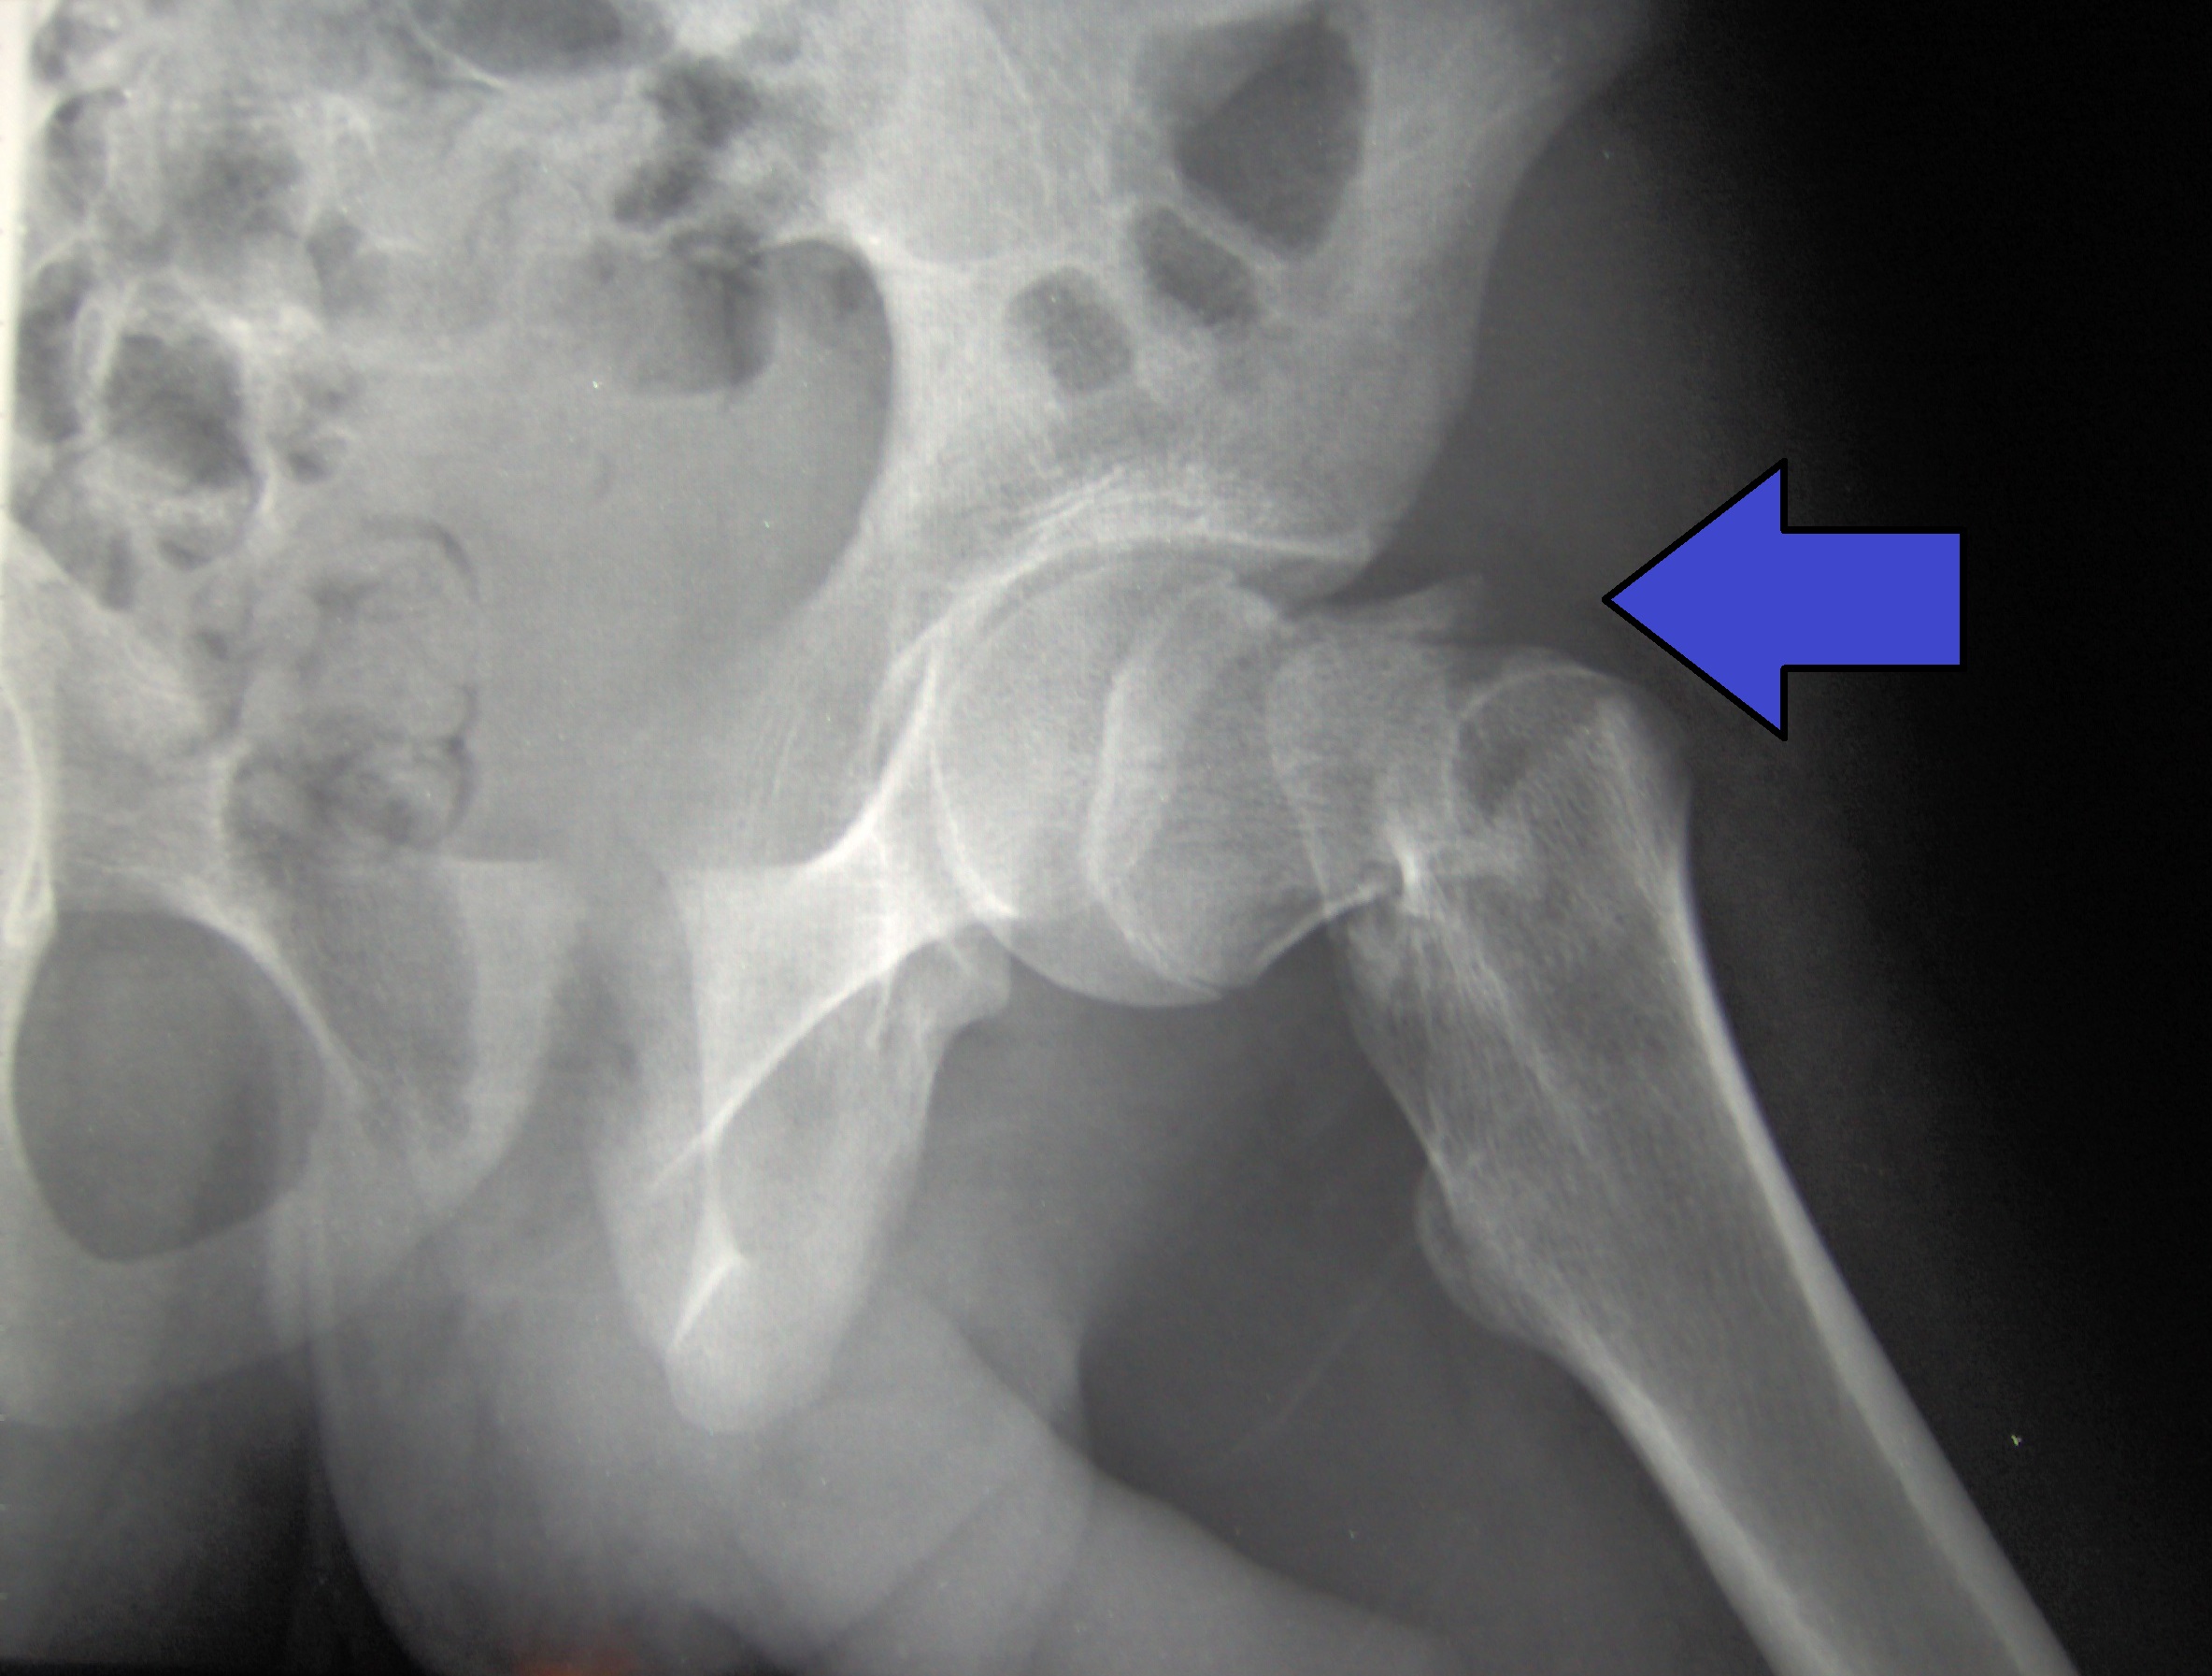

Esta revisión sistemática mostró beneficio de una variedad de tratamientos para la osteoporosis en mujeres posmenopáusicas, con reducción de fracturas clínicas y vertebrales. Los tratamientos anabólicos óseos fueron más efectivos que los bisfosfonatos en la prevención de fracturas clínicas y vertebrales, independientemente de los indicadores de riesgo basales, por lo que se considera que no hay evidencias para  restringir el uso del tratamiento anabólico a pacientes con un riesgo muy alto de fracturas. Sinembargo, la certeza en las estimaciones del efecto fue de moderada a baja para todos los resultados individuales, lo que indica un riesgo grave de sesgo e imprecisión. BMJ, 2 de mayo de 2023.

Actualización de las recomendaciones del ACP sobre el tratamiento de la osteoporosis

El American College of Physicians (ACP) ha publicado una revisión de su guía de 2017 sobre el tratamiento de la osteoporosis primaria o de la baja masa ósea en adultos de ambos sexos. El uso de bifosfonatos en mujeres postmenopáusicas es la única recomendación fuerte, con certeza de evidencia alta, para tratar la osteoporosis primaria. En contraste, la indicación de bifosfonatos en hombres o de denosumab, romosozumab o teriparatida, son todas recomendaciones condicionales. Finalmente, se sugiere un enfoque personalizado para decidir el uso de bifosfonatos en mujeres mayores de 65 años con osteopenia. Annals of Internal Medicine, 3 de enero de 2023.